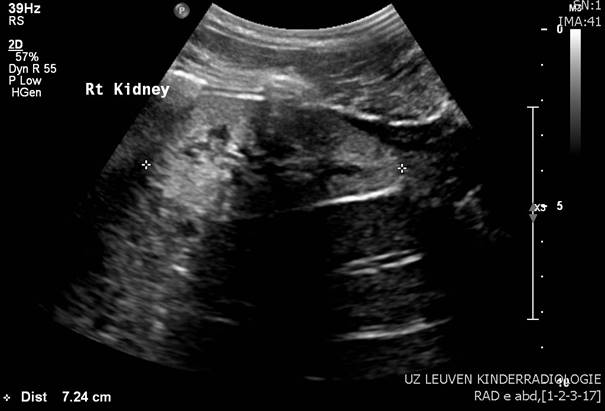

Abdominal U/S showed bilateral renal dysplasia (small, hyperechogenic kidneys).